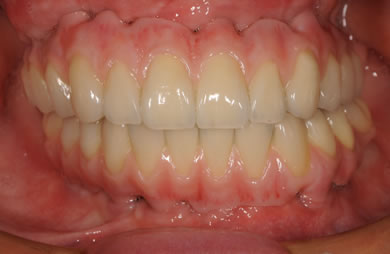

骨再生スピードインプラント治療+AGC連結セラミック治療

| 治療方針 | 骨再生療法にて骨量を回復するとともに軟組織も移植し、機能的回復だけでなく審美的回復も行う。 | ||||||||||||||||||||||||||||||||

| 治療内容 | インプラント12本(サイナスリフト+GBR+抜歯即日スピードインプラント+遊離歯肉移植)、AGCハイブリッドセラミック連結ブリッジ2装置(上顎・下顎)、テンポラリーインプラント2本 | ||||||||||||||||||||||||||||||||

| 総治療費 | 6,019,650円 | ||||||||||||||||||||||||||||||||

| 治療期間 | 1年0ヶ月 |